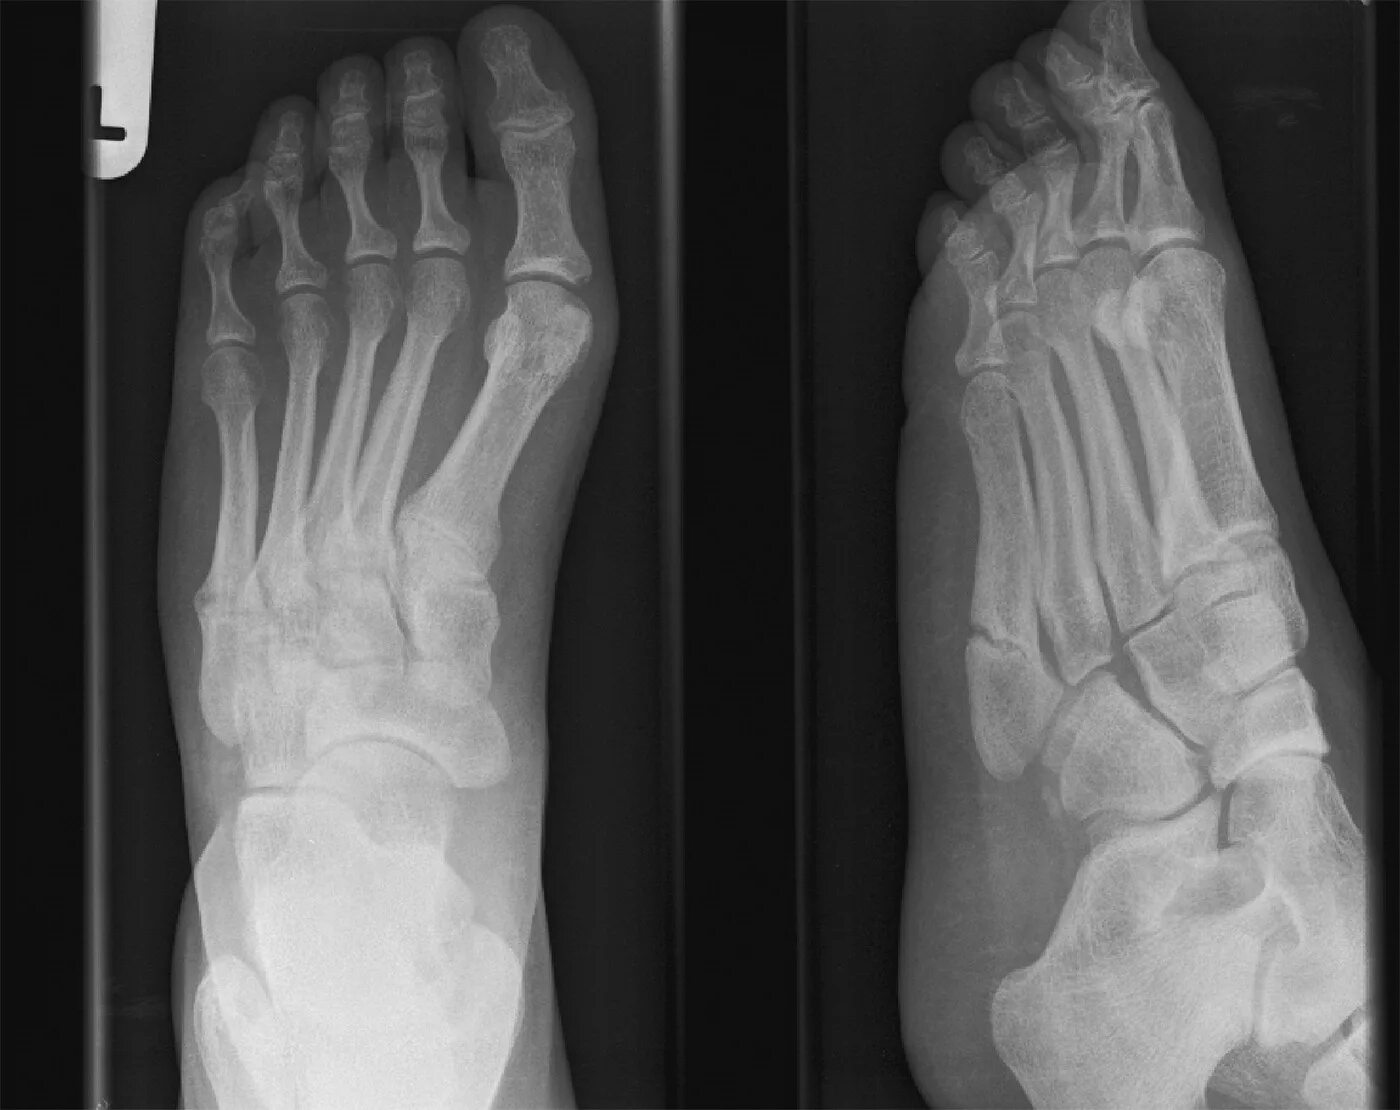

Перелом задней кости стопы